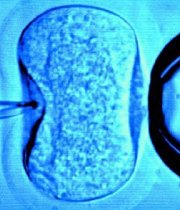

ImagenLa diputada RN Karla Rubilar, integrante de la comisión de Salud de la Cámara Baja, lamentó el mínimo acceso que existe a la posibilidad de la fertilización asistida a las parejas que no pueden concebir, que actualmente -afirmó- son entre el 10 y el 15 por ciento del total.

Según el ginecólogo José Balmaceda, de la Sociedad Chilena de Fertilidad, es preocupante que en las propuestas de los presidenciables no haya referencia a la fertilidad, porque por ejemplo en los programas gratuitos, el acceso es sólo de un 0,1 por ciento, con sólo 200 cupos anuales y "hay una lista de espera bastante significativa".